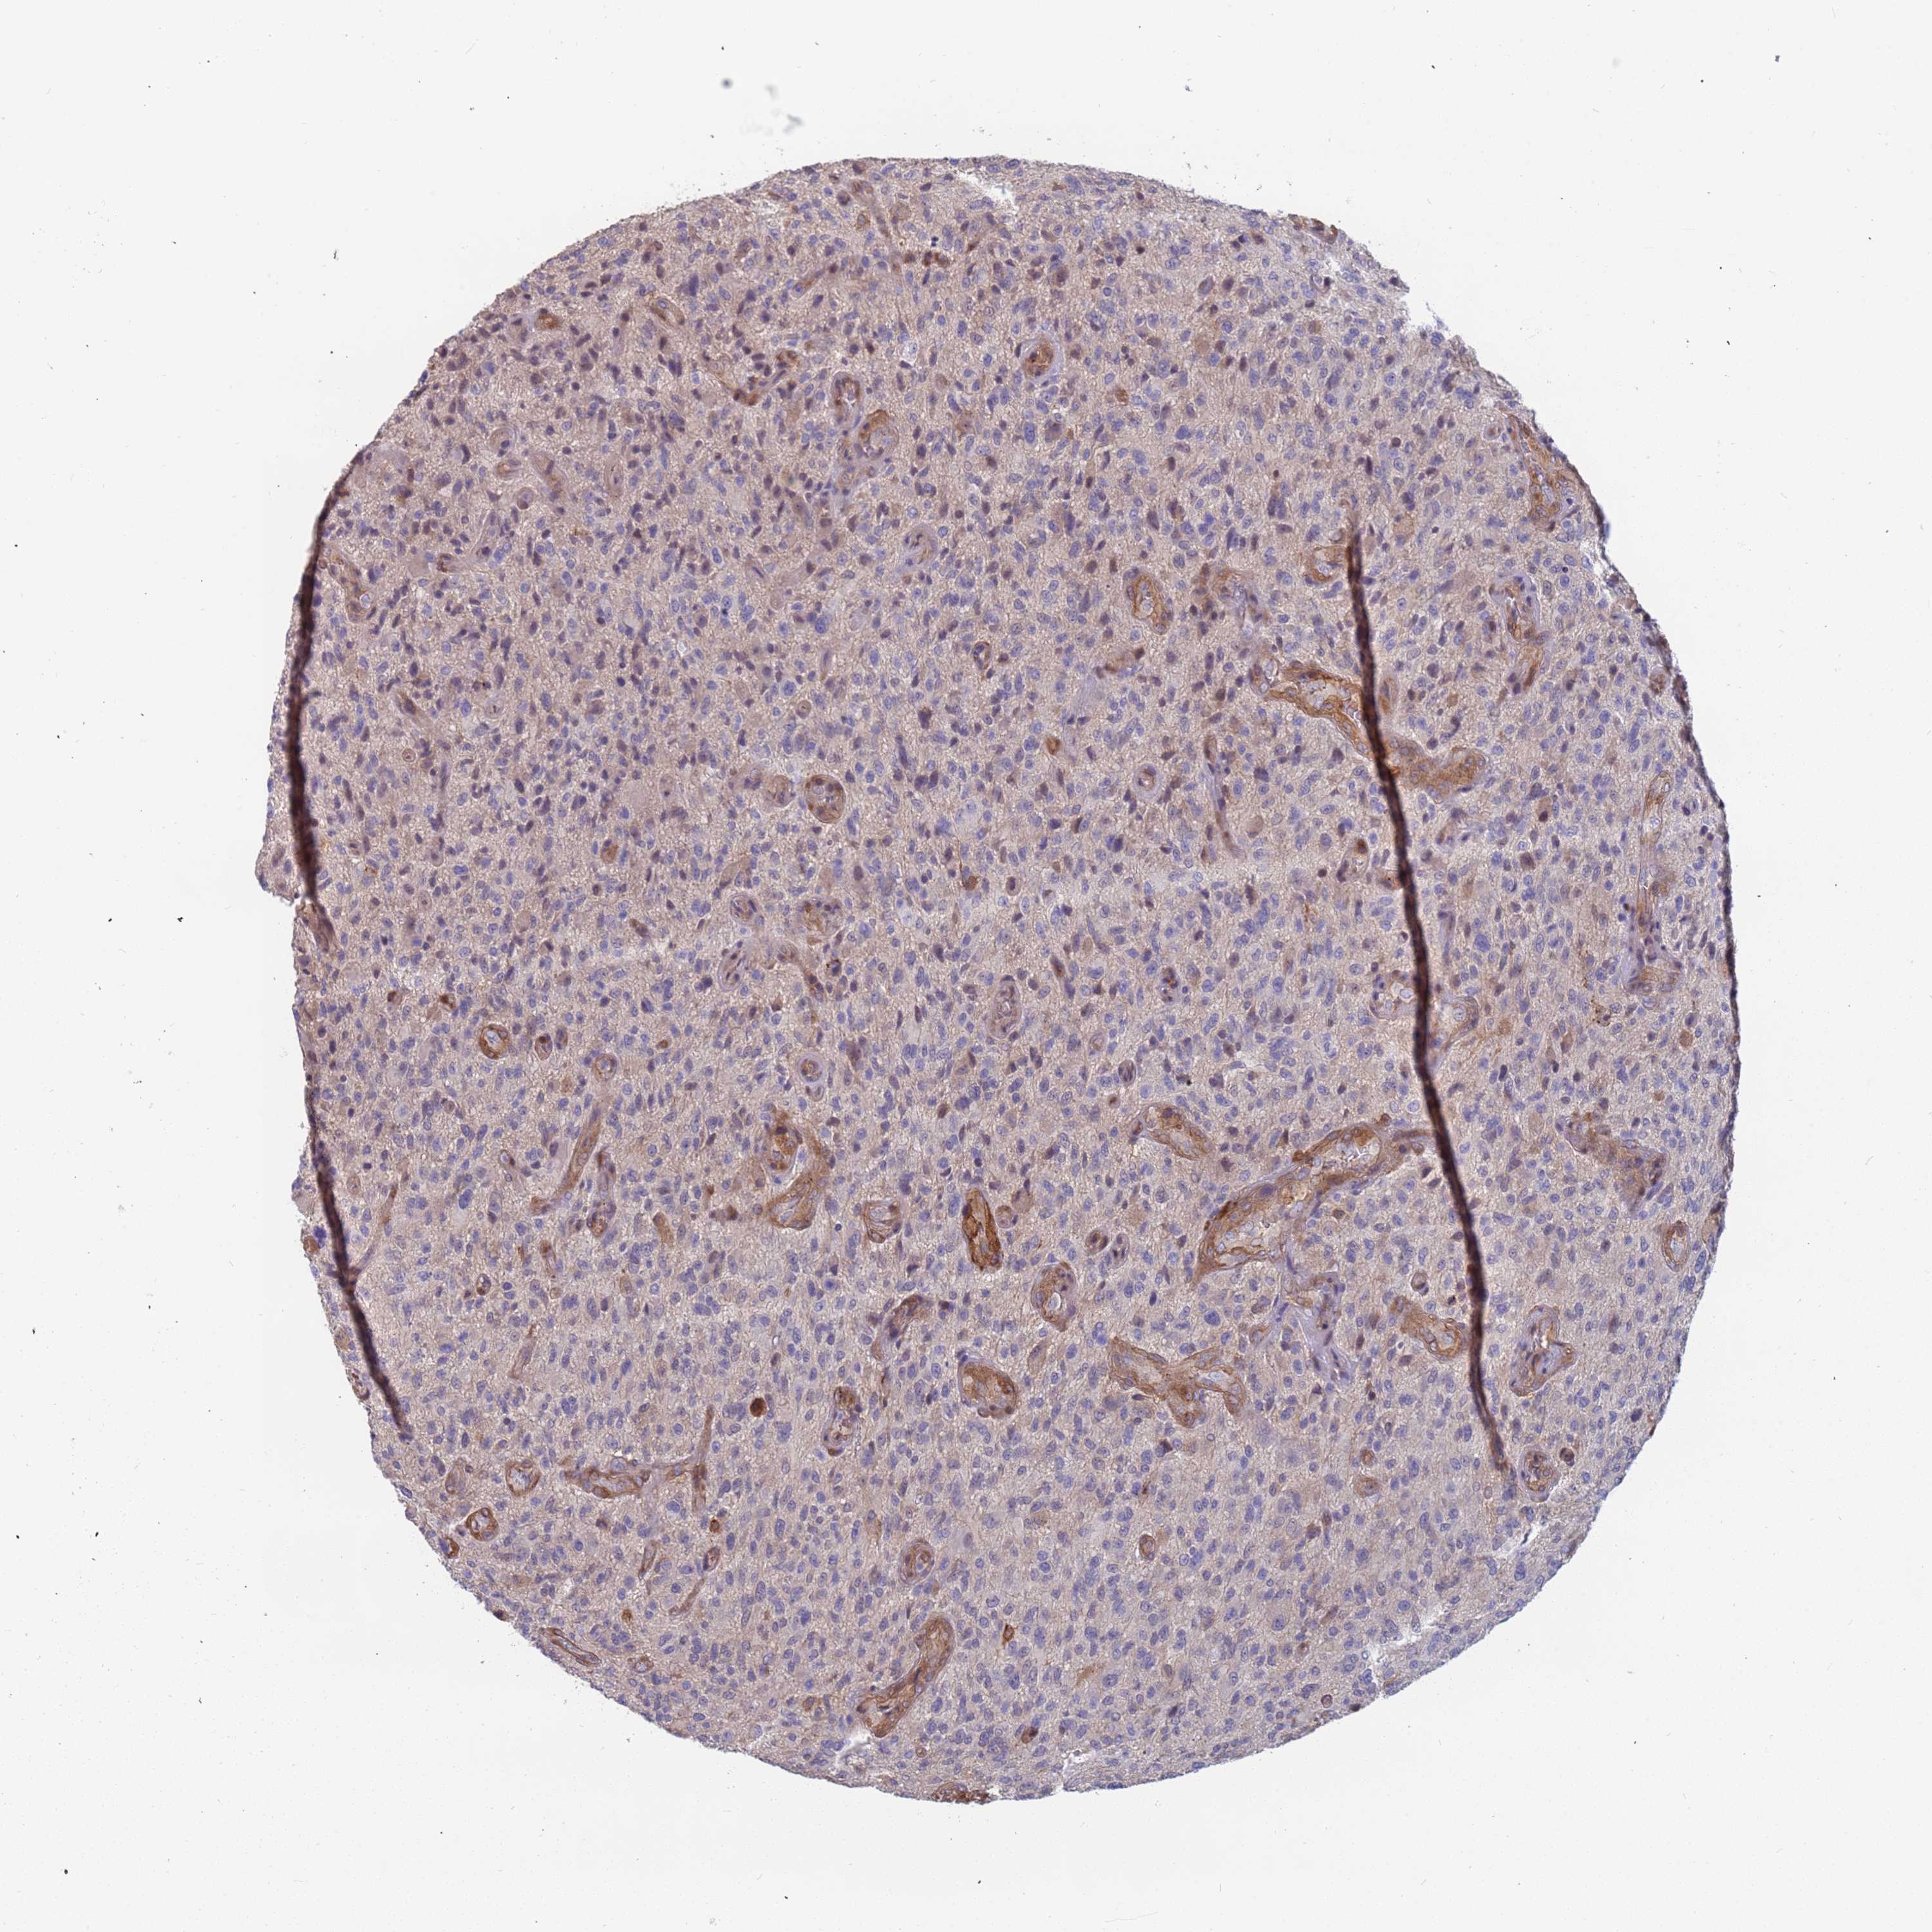

GLIOMA - Protein expressioni

A mouse-over function shows sample information and annotation data. Click on an image to view it in a full screen mode. Samples can be filtered based on level of antibody staining by selecting one or several of the following categories: high, medium, low and not detected. The assay and annotation is described here.

Note that samples used for immunohistochemistry by the Human Protein Atlas do not correspond to samples in the TCGA dataset.

Antibody stainingi

Antibody staining in the annotated cell types in the current human tissue is reported as not detected, low, medium, or high, based on conventional immunohistochemistry profiling in selected tissues. This score is based on the combination of the staining intensity and fraction of stained cells.

Each image is clickable and will lead to virtual microscopy that enables deeper exploration of all samples and also displays staining intensity scores, fraction scores and subcellular localization as well as patient and tissue information for each sample.

Antibody HPA047394

Antibody HPA049890

Antibody HPA049986

Staining

High

Medium

Low

Not detected

Intensity

Strong

Moderate

Weak

Negative

Quantity

>75%

75%-25%

<25%

None

Location

Nuclear

Cytoplasmic/membranous

Cytoplasmic/membranous,nuclear

Glioma, malignant, High grade

Glioma, malignant, Low grade